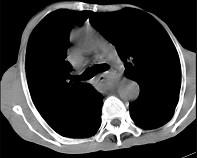

问题 女,71岁,进食时有梗阻感,进行性加重半年,影像检查如图,最可能的诊断是 ( )

选项 A.贲门失弛缓症 B.食管癌并纵隔淋巴结转移 C.食管良性狭窄 D.反流性食管炎 E.食管静脉曲张

答案 B